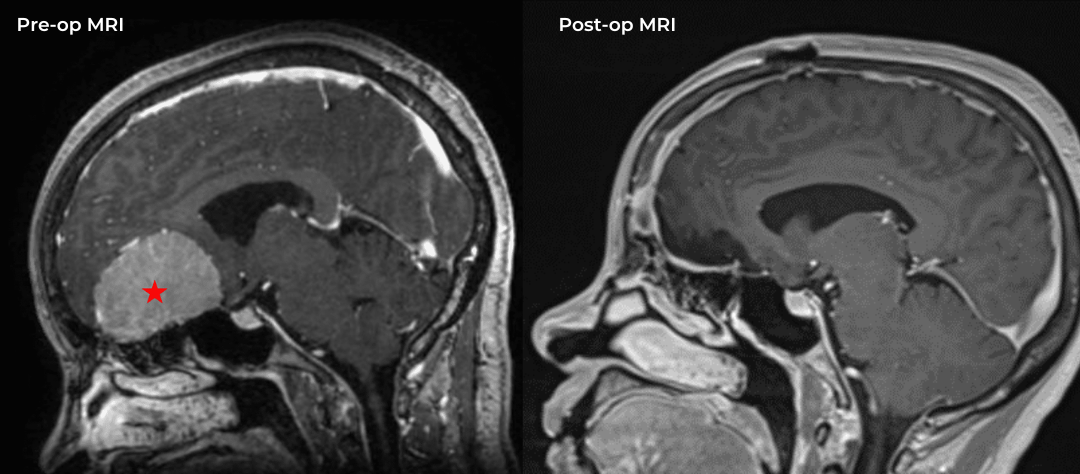

This is a 49-year-old otherwise healthy female who presented with bifrontal and retro-orbital headaches, behavioral changes, and forgetfulness. Symptoms have been progressively worsening over the past month. Her neurologic exam revealed a pronator drift, otherwise was unremarkable. MRI brain demonstrated a large extra-axial homogeneously enhancing mass of the anterior cranial fossa, resulting in significant mass effect and vasogenic edema (Figure 1a and 2a). Imaging was most consistent with a planum sphenoidale meningioma. She was referred to Dr. Xavier Gaudin for neurosurgical evaluation.

Figure 1a – Preoperative MRI demonstrating an extra-axial enhancing mass of the anterior cranial fossa.

Figure 1b – Postoperative MRI demonstrating a complete resection without residual enhancement.

She was started on high-dose steroid and antiseizure prophylactic medicine. Surgical intervention was offered for mass effect, symptomatic relief, neurologic preservation, and histopathologic diagnosis. Dr. Gaudin performed a bifrontal craniotomy with complete resection of neoplasm through an interhemispheric and subfrontal approach. Postoperative imaging demonstrated a gross total resection without residual tumor and resolution of mass effect (Figure 1b and 2b). Intraoperative pathology was consistent with meningioma, WHO grade 1. She recovered very well, and was discharged home on postoperative day 3. On her follow-up outpatient visit, her preoperative symptoms had fully resolved, and her olfactory sense was maintained.